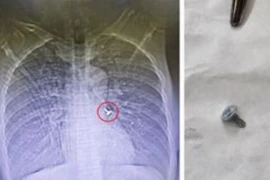

Đinh vít nhọn lạc trong phế quản người đàn ông 61 tuổi

Dị vật khi xâm nhập vào đường thở tùy thuộc vào vị trí bị mắc kẹt mà triệu chứng biểu hiện khác nhau dễ gây bít đường thở, thậm chí tử vong trong thời gian ngắn.